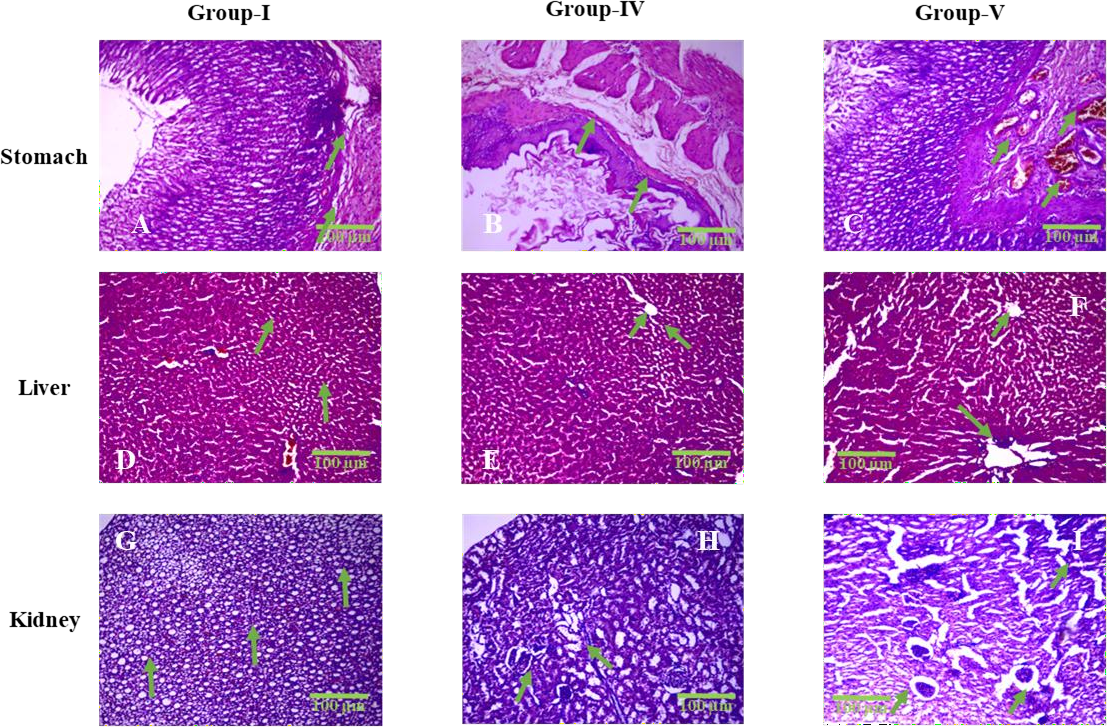

Fig. 3: Representative histopathological sections of the stomach, liver, and kidney from Group I (Control), Group IV (High Dose MF-ZnO-NPs), and Group V (Raw Miltefosine), stained with hematoxylin and eosin (HandE) and observed under 400× magnification. All images include 100 µm scale bars for reference. In the stomach sections (A–C), Group I displays intact mucosal epithelium and submucosa with no pathological changes (green arrows indicate preserved epithelial lining), whereas Group IV shows mild to moderate epithelial disruption and submucosal edema (B; green arrows mark mucosal folding and thinning), and Group V reveals severe epithelial erosion and dense inflammatory infiltration (C; green arrows indicate ulcerated regions and infiltrating leukocytes), corresponding to semi-quantitative inflammation scores of 0, 1–2, and 3, respectively. In the liver sections (D–F), Group I exhibits normal hepatic cords and central veins (green arrows in D), Group IV presents moderate hepatocellular degeneration and sinusoidal dilation (E; green arrows highlight swollen sinusoids), and Group V shows extensive centrilobular necrosis, sinusoidal congestion, and lymphocytic infiltration (F; green arrows indicate necrotic foci and disrupted hepatic cords), corresponding to necrosis scores of 0, 2, and 3. In the kidney sections (G–I), Group I demonstrates intact glomeruli and tubular structures (green arrows in G), Group IV exhibits moderate tubular degeneration and interstitial inflammation (H; green arrows highlight tubular dilation and interstitial cell infiltration), and Group V shows severe peri-glomerular inflammation, glomerular hypercellularity, and loss of tubular integrity (I; green arrows indicate pathological glomerular changes), with semi-quantitative scores ranging from 0 to 3. These histological findings visually support the graded tissue-level toxicity observed across treatment groups and reinforce the protective effect of MF-ZnO-NPs compared to raw miltefosine

Histopathological examination of gastric tissues revealed a graded pattern of mucosal response across treatment groups, summarized in table 6. Group I (Control) exhibited normal gastric histoarchitecture with an intact epithelial lining and no signs of inflammation or tissue disruption, indicating the absence of gastric toxicity (scores: epithelial disruption = 0, inflammation = 0). Group IV (High Dose MF-ZnO-NPs) showed mild toxicity characterized by subtle mucosal changes and mild epithelial irregularity, with a score of 1 for epithelial disruption and 1 for inflammation. Group V (Raw Miltefosine) displayed the most pronounced gastric alterations, including epithelial disruption (score = 2) and marked inflammatory cell infiltration (score = 3) within the mucosa, consistent with mucosal irritation and early signs of ulceration.

The histopathological evaluation of hepatic tissues revealed a progressive pattern of liver alterations correlating with dose intensity. Group I (Control) displayed completely normal hepatic architecture (scores: necrosis = 0, inflammation = 0). Group II (Low Dose MF-ZnO-NPs) and Group III (Medium Dose MF-ZnO-NPs) showed mild sinusoidal dilation and scattered hepatocellular changes (scores ranging from 0–1 and 1, respectively). Group IV (High Dose MF-ZnO-NPs) demonstrated moderate hepatocellular degeneration, sinusoidal congestion, and focal necrosis (score = 2 for both necrosis and inflammation). In contrast, Group V (Raw Miltefosine) exhibited extensive centrilobular necrosis, pronounced sinusoidal congestion, and widespread inflammatory infiltration, reflected by the highest scores (3 for both necrosis and inflammation). These findings confirm a clear dose-dependent hepatotoxic response, with the nanoparticle formulation offering relative hepatic protection compared to the free drug.

Histopathological assessment of renal tissues revealed similar dose-correlated trends. Group I (Control) showed preserved glomeruli and intact tubular structures without inflammatory changes (scores: tubular degeneration = 0, inflammation = 0). Group II and Group III displayed minor interstitial edema and mild cellular degeneration (scores 0–1 and 1–2, respectively), indicative of a mild adaptive tissue response. Group IV (High Dose MF-ZnO-NPs) exhibited moderate tubular degeneration and interstitial inflammation (scores 2–3 for degeneration, 2 for inflammation), while Group V (Raw Miltefosine) demonstrated severe peri-glomerular inflammation, glomerular hypercellularity, and pronounced tubular damage (score = 3 for both parameters), confirming significant nephrotoxic insult.

All histopathological sections were evaluated under 400× magnification using high-resolution imaging shown in fig. 3. Each fig. included 100 µm scale bars and clearly annotated histological landmarks such as hepatocellular necrosis, tubular lysis, glomerular congestion, and epithelial disruption, thereby enhancing interpretability.